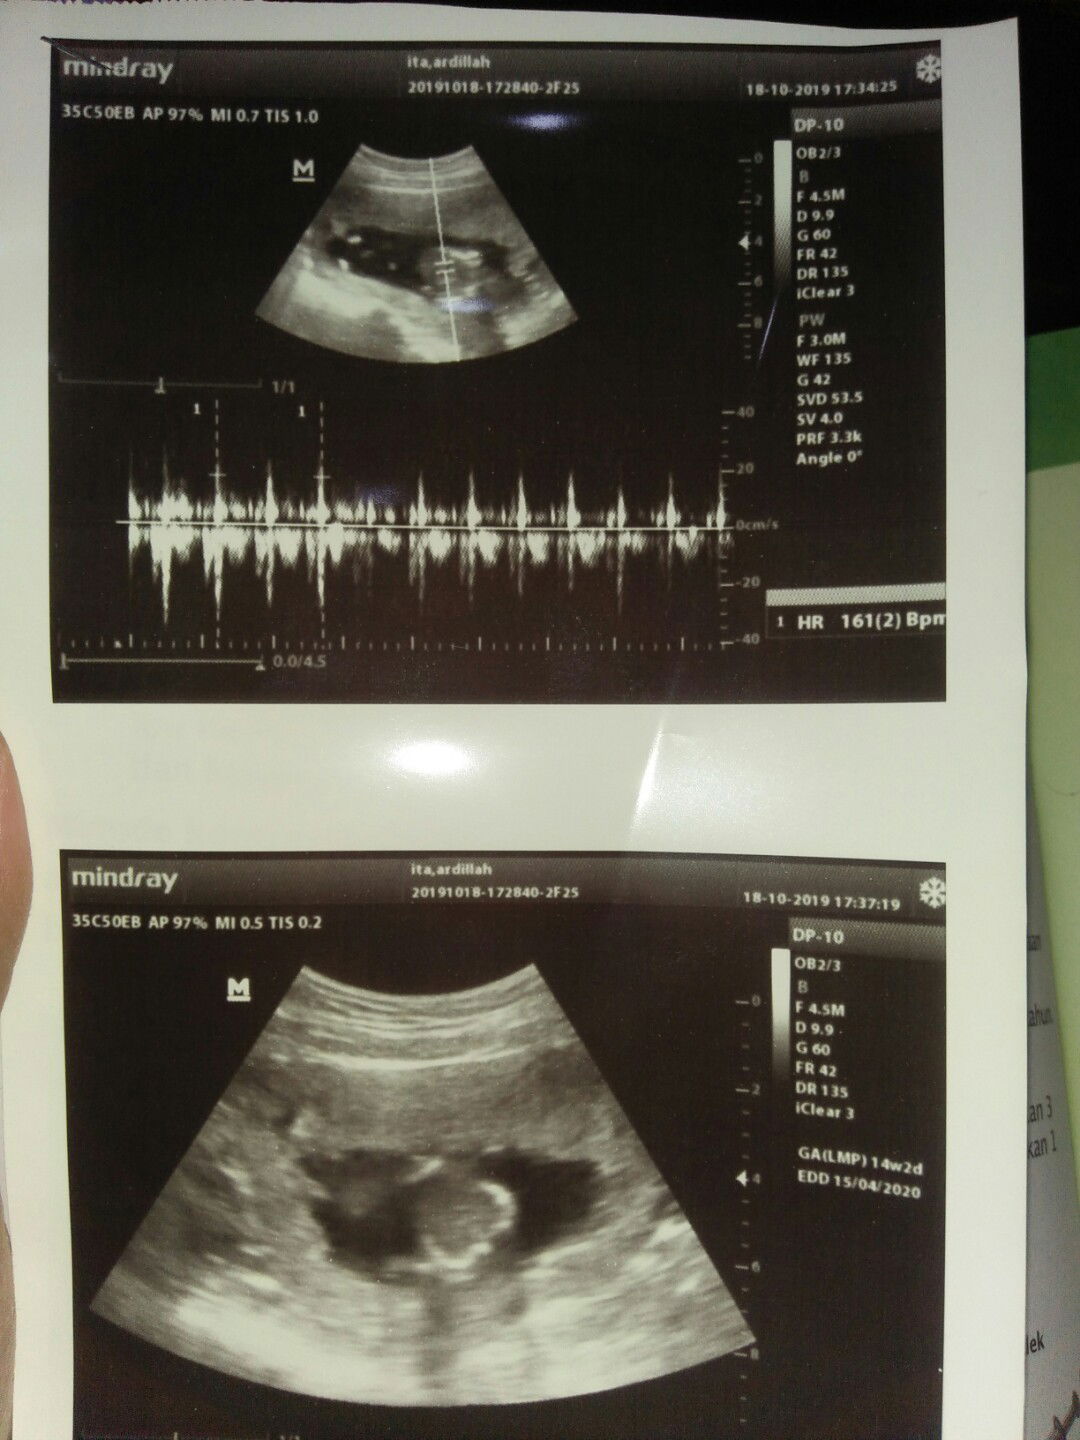

tany USG

Hay bun/mom, mau tanya ini itu usg yg 2D/3D ya, trus bisa d bwt ngliat jnis kelamin ngga.,, jenis kelamin bisa d lihat UK brapa ya bund?, trimakasih